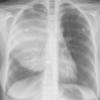

Lymphoma -Mediastinal and left axillary nodes (see CT)

Date: 04/01/2014

Views: 2590